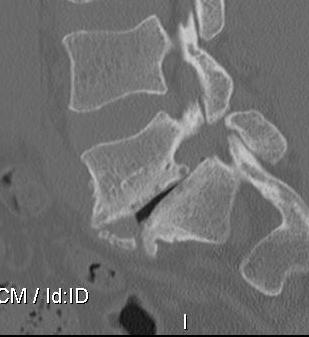

CT scan

Technique

- reverse gantry

Indication

- perform instead of obliques

- oblique x-rays have high radiation dose with little extra information compared with CT